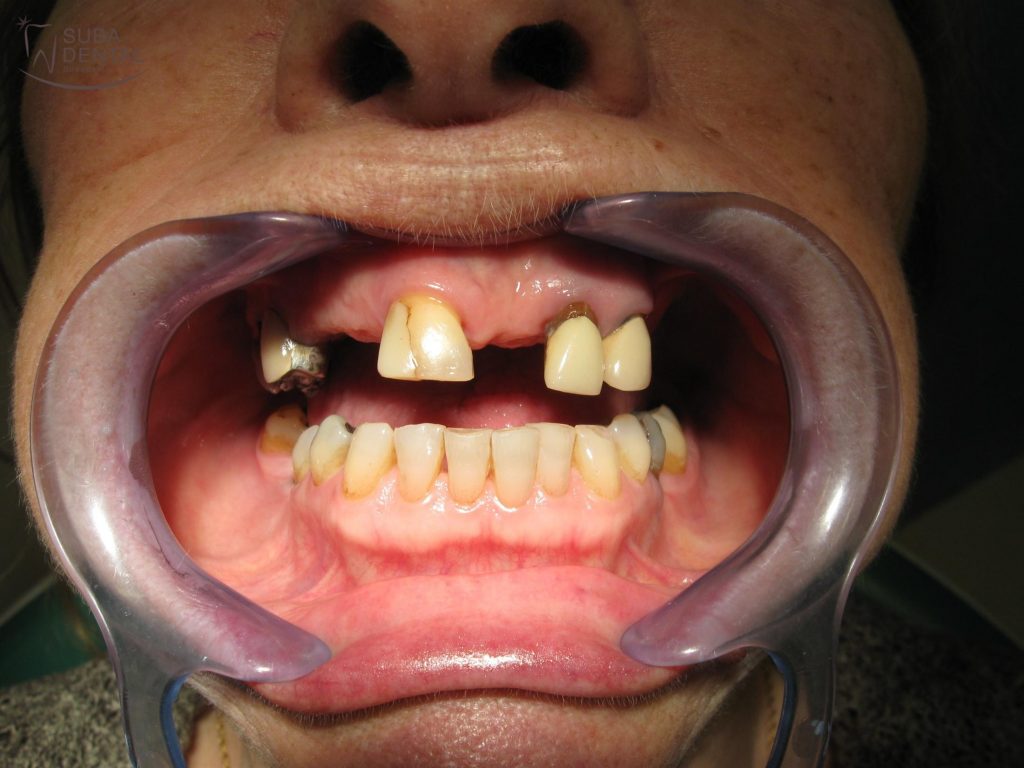

74 éves nő páciensünk a következő panaszokkal, illetve kérésekkel fordult a Suba Dentál rendelőhöz:

- Felső fogai közül jó néhányat elvesztett, és egy kapcsos fogsort készítettek a számára, melyet nem tudott megszokni.

- Esztétikusabb, fix pótlást szeretne.

- Örülne, ha fogai fehérebbek lennének.

- Az implantátumok beültetésétől nem zárkózik el, de a csontpótlástól idegenkedik.

Az első konzultáció alkalmával a panorámaröntgen alapján alaposan megvizsgáltuk a fogak állapotát. CBCT (Cone beam computed tomography) felvétel alapján pontosan láthatóvá vált, hogy a csontkínálat megfelelő ahhoz, hogy az hiányzó jobb alsó őrlőket implantátumokkal pótoljuk. A bal felső régióban viszont az implantátumokkal való pótlás csak csontpótlással (sinus lift) lehetséges, melyet páciensünk nem szeretett volna.

Az első kezelés alkalmával fogkőeltávolítást, és rendelői Zoom fogfehérítést végeztünk, valamint az alsó hiányzó őrlőfogak helyére oldalanként 2 implantátumot helyeztünk be.

Régi, kivehető felső fogsora, mellyel sosem tudott megbarátkozni